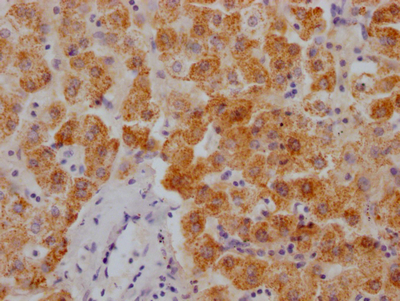

The image on the left is immunohistochemistry of paraffin-embedded Human liver cancer tissue using CSB-PA985822(ATP2A3 Antibody) at dilution 1/30, on the right is treated with synthetic peptide. (Original magnification: ×200)